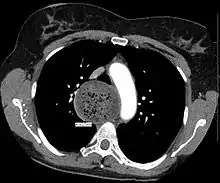

An axial CT image showing marked dilatation of the esophagus in a person with achalasia.

Due to the similarity of symptoms, achalasia can be mistaken for more common disorders such as gastroesophageal reflux disease (GERD), hiatus hernia, and even psychosomatic disorders. Specific tests for achalasia are barium swallow and esophageal manometry. In addition, endoscopy of the esophagus, stomach, and duodenum (esophagogastroduodenoscopy or EGD), with or without endoscopic ultrasound, is typically performed to rule out the possibility of cancer.[9] The internal tissue of the esophagus generally appears normal in endoscopy, although a "pop" may be observed as the scope is passed through the non-relaxing lower esophageal sphincter with some difficulty, and food debris may be found above the LES.